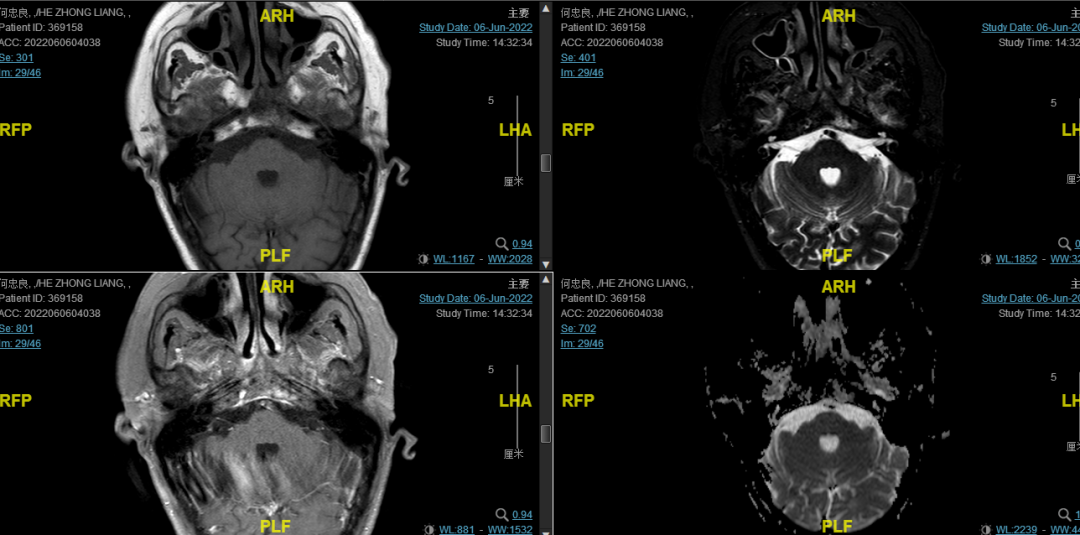

后患者至江苏省肿瘤医院放疗科就诊,2022-06-06完善头颅MR检查:

修正诊断:鼻咽癌T3N1M0,Ⅲ期。

2022-08-05(放疗近结束)复查MR,疗效评价:CR。鼻咽部肿物及咽后转移淋巴结颈部转移淋巴结均达到CR。